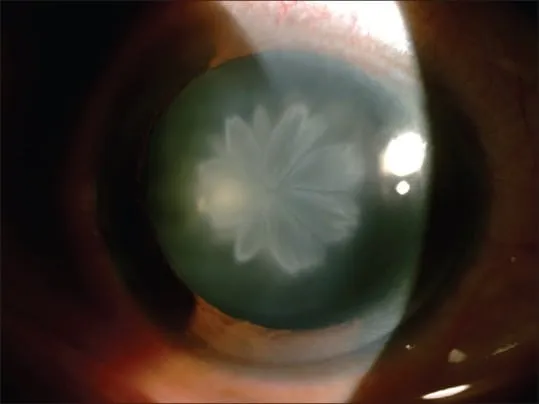

- Rosette/Stellate Cataract: Pathognomonic. Anterior/posterior subcapsular. Forms hours to days.

⭐ A classic rosette-shaped or stellate cataract is highly characteristic of concussional trauma and typically forms within hours to days post-injury.

- Rosette-shaped cataract is a hallmark of blunt ocular trauma.